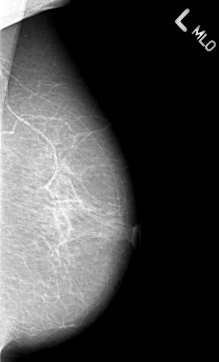

B_3013_1.LEFT_MLO

LEFT_MLO LINES 4344 PIXELS_PER_LINE 2624 BITS_PER_PIXEL 12 RESOLUTION 50 NON_OVERLAY

FILE: B_3013_1.RIGHT_MLO.OVERLAY

TOTAL_ABNORMALITIES 2

ABNORMALITY 1

LESION_TYPE MASS SHAPE IRREGULAR-ARCHITECTURAL_DISTORTION MARGINS SPICULATED

ASSESSMENT 5

SUBTLETY 5

PATHOLOGY MALIGNANT

ABNORMALITY 2